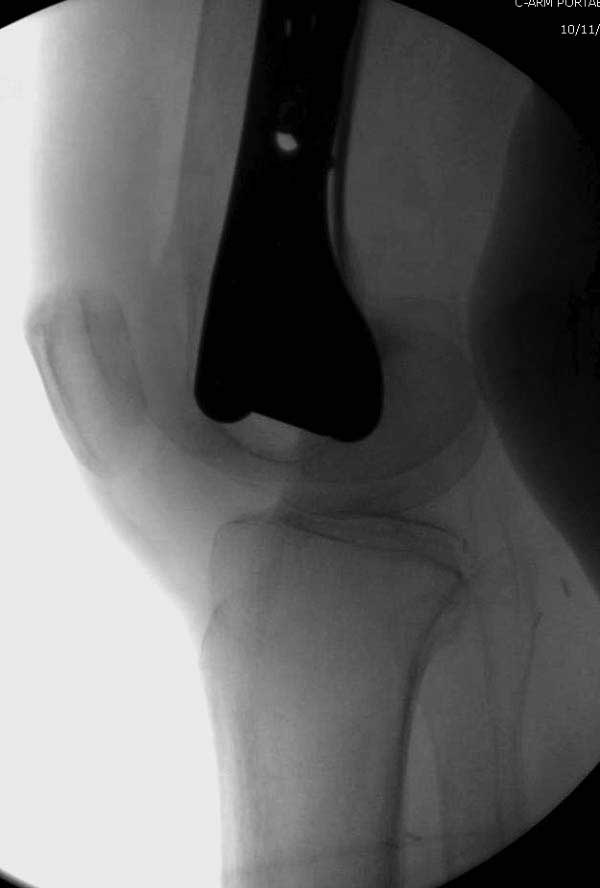

Обычно после чрезвертельных переломов, за исключением молодых, у пожилых остается нестабильность при движении. Часто падают и после 3х мес. в результате падения обнаружен перипротезный перелом (22-23), который зафиксирован Синтез пластиной.

Имя     : 23 distal fem fx.lat.jpg

Тип     : image/jpg

Размер  : 26162 байтов

Описание: отсутствует

Url     : http://weborto.net:8080/pipermail/ortho/attachments/20120509/52aada75/attachment-0045.jpg